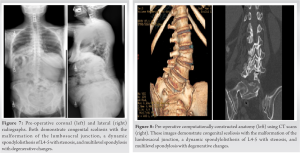

Neurologic examination revealed 4/5 motor grade in bilateral EHL but was otherwise intact. The patient opted to proceed with surgical intervention. Pre-operative radiographs (Fig. 7) and CT scan (Fig. 8) demonstrated CS with malformation of the lumbosacral junction, a dynamic spondylolisthesis of L4-5 with stenosis, and multilevel spondylosis with degenerative changes. The index operation consisted of TLIF at L4-5, and T10-pelvis PSF using a standard posterior interbody titanium implant at L4-L5. Cobalt chromium rods were utilized in the index surgery. 1 year postoperatively, she developed a pseudoarthrosis at L4-5 along with bilateral rod fractures at the lumbosacral junction, leading to lumbosacral pain, along with progressive sacroiliac joint dysfunction (Fig. 9). She underwent revision posterior spinal fusion consisting of revision iliac fixation, additional iliac fixation with an accessory rod on fractional curve side, and bilateral sacroiliac joint stabilization and fusion (Fig. 10). Following surgery, she reported resolution of back and leg pain and markedly improved function compared to before initial index surgery.

The objectives of this study were to (1) illustrate an example of successful surgical treatment of a patient with hemivertebrae using custom patient-specific implants at multiple spinal levels and (2) compare this case a to a similar case that utilized standard implants. The patient in Case 1 suffered from chronic low back pain due to CS and a right wedge vertebra. Following lumbar decompression and fusion using customized 3D-printed implants, the patient reported significant improvement in her pain and posture (Fig. 6). Given the anatomic complexity of these patients, the development and utilization of customized implants allowed for an excellent endplate apposition without the need for extensive bony resection, which would not be possible with standard interbodies. To our knowledge, this is the first reported case demonstrating the treatment of CS using 3D-printed personalized spinal implants for multiple spinal levels. Studies evaluating the efficacy of personalized spinal implants are largely limited to case studies. Two of these studies reported the use of these implants in the treatment of congenital spinal disorders. Mobbs et al. [14] presented a 52-year-old woman with an 18-month history of back pain. Similar to our patient, their patient was found to have a congenital hemivertebra at L5 (Fig. 1 and 2) with degenerative changes that was treated with lumbar decompression and fusion with a personalized spinal implant. However, while only the L4/L5 segment was fused in Mobbs et al. case, the patient in our case underwent L3-S1 ALIF and posterior instrumentation T10-Pelvis (Fig. 4 and 5), demonstrating increased severity and unique complexity in our case. In another study [15], a 34-year-old man presented with a 3-year history of bilateral L5 radiculopathy caused by bilateral L5 pars defect, L5/S1 degenerative disc disease, and severe foraminal stenosis. Anterior lumbar interbody fusion surgery was performed with custom 3D interbodies. Again, our case differed from this case in complexity of procedure and medical history as we performed a multilevel deformity surgery using multilevel customized implants. To address our second objective, we compared Case 1 to Case 2, where the patient underwent an index lumbar decompression and fusion for CS (Fig. 7 and 8) using standard titanium implants. At 2-year post-operative, the patient in Case 2 presented with worsening sacroiliac pain with the evidence of rod fracture and pseudoarthrosis at L4-L5 (Fig. 9). Revision surgery resulted in improved pain and mobility (Fig. 10). Development of pseudoarthrosis and the need for revision surgery in Case 2 may be explained by the decreased surface area available for fusion, decreased contact of the implant with the bone, thus decreased on-growth and through-growth resulting in decreased osteointegration, and stability as compared to Case 1, which utilized custom implants. While larger, randomized, controlled studies are still needed to gain knowledge pertaining to long-term outcomes in comparison to traditional, non-customized implants, existing biomechanical and animal investigations of customized implants suggest they will provide improved outcomes and increased surgical safety and efficiency. In a study evaluating the biomechanical properties of titanium cages in cervical spine surgery, Fengbin et al. found that implants with increased end plate contact surface area resulted in decreased loss of height of fused segments, lower rate of subsidence, and lower scores of neck pain [16]. During an en bloc resection of L5 vertebral body with single lesion, Mobbs et al. compared reconstruction using a 3D patient-specific implant and an off-the-shelf implant at the same spinal level intraoperatively. The 3D patient-specific implant resulted in decreased time to implant, reduced radiographs required to determine the position of implant, improved end plate fit, and more uniform loading compared to the off-the-shelf implant [5]. From a safety perspective, 3D-implants seem to provide benefit over off-the-shelf implants as they avoid osteotomies required with off-the-shelf implants, thus decreasing operative time and blood loss, as well as allow for pre-planned screw trajectories which decrease the chance of damage to blood vessels, nerves, and the spinal cord [17]. The utility of 3D customized implants in allowing surgeons to operate on native anatomy will be safer, quicker, and result in increased osteointegration and bone/implant interface.